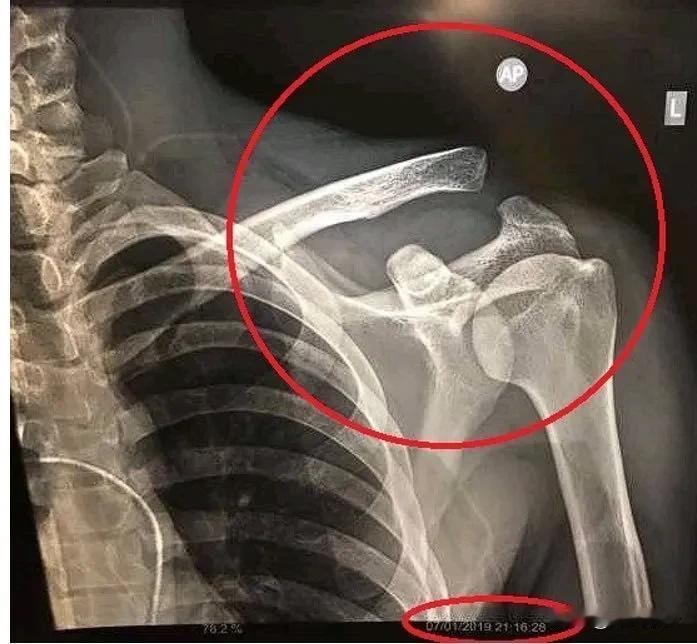

今晚18:30足协杯决赛,山东泰山对阵上海海港。赛前外界的关注点主要集中在随队前往温州的海港前锋武磊身上。 武磊作为中超赛场上的超级射手,一直在国家队被寄予厚望,但不是为武磊开脱,他也确实为国家队付出了很多,不知道大家还记得否?他在去西班牙之前吧,曾经肩膀骨折忍痛为国足单场比赛打进两球。这种疼痛一般人都会疼晕,他却还能为国家队拼命,所以现在诈伤是不太可能的。 不过现在,他在伊万的战术中有些“鸡肋”,他的存在反而让伊万为难,因为他的实力无疑是外援级别的,但他的特点不适合目前的国足,张玉宁、拜合拉木、林良铭,甚至是王子鸣都逐渐在伊万的战术中获得重要位置,即便以后武磊回归,他也很可能在70-80分钟时替补上场,主力很难了。 所以,希望大家还是关注足协杯决赛的比赛本身,山东泰山在足协杯比赛上的经验丰富,即便实力上或许稍逊海港,但经验和斗志或许会弥补这些因素,看好山东泰山小胜。 关注足协杯 浅析足协杯 足协杯关注